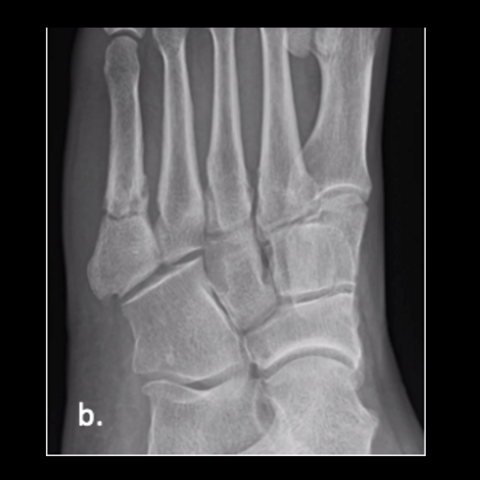

Figure 1b

Figure 1b. A 23-year-old male trainee twisted his foot while running, presenting a week or 2 later. Here is an injury film.